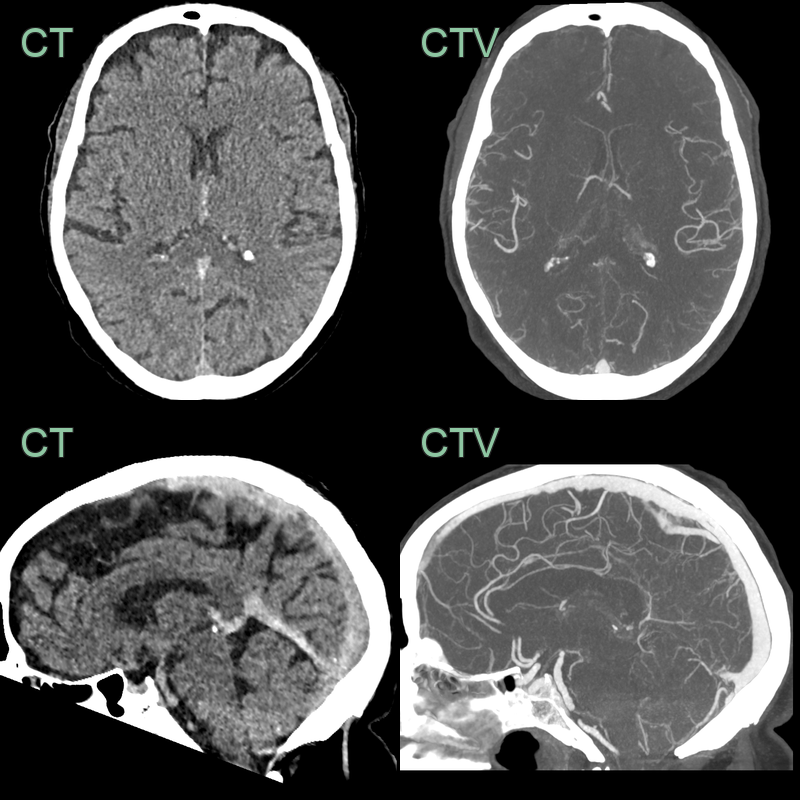

- 50-year-old patient presented with headache and dysphasia.

- CT showed a hyperdense superior sagittal sinus and a lobulated, fractionated, haematoma in the left parietal and occipital lobe.

- Despite a successful venous thrombectomy, thrombus reaccumulated in the superior sagittal sinus and the haematoma enlarged.